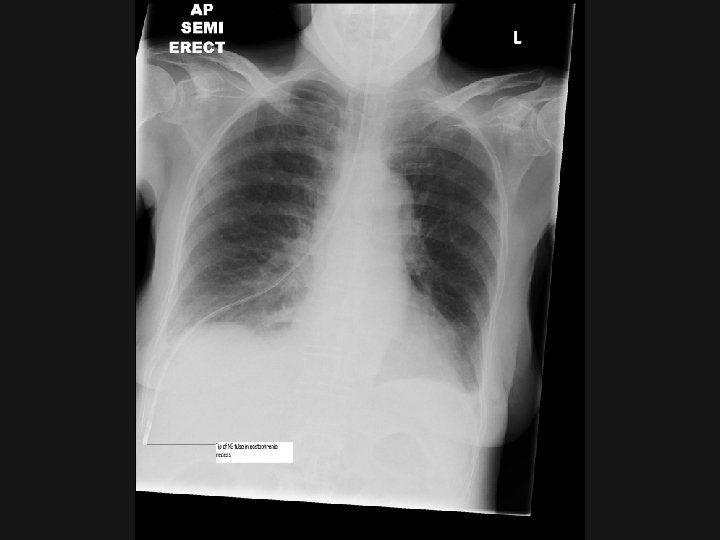

Routes Of feeding

Naso-gastric Feeding n n n Risk of aspiration in ICU: HOB 30 degrees Don’t start feed at night Risk of displacement High aspirates and inadequate calories common in ICU PEG/gastrostomy feeding for long-term

Jejunal Feeding n n n Jejunal feed: via a tube placed Trans-nasally by endoscopy, radiologically, at the bedside. Into the jejunum either at laparotomy or laparoscopy May reduce incidence of aspiration Often increases dose of EN given over NG